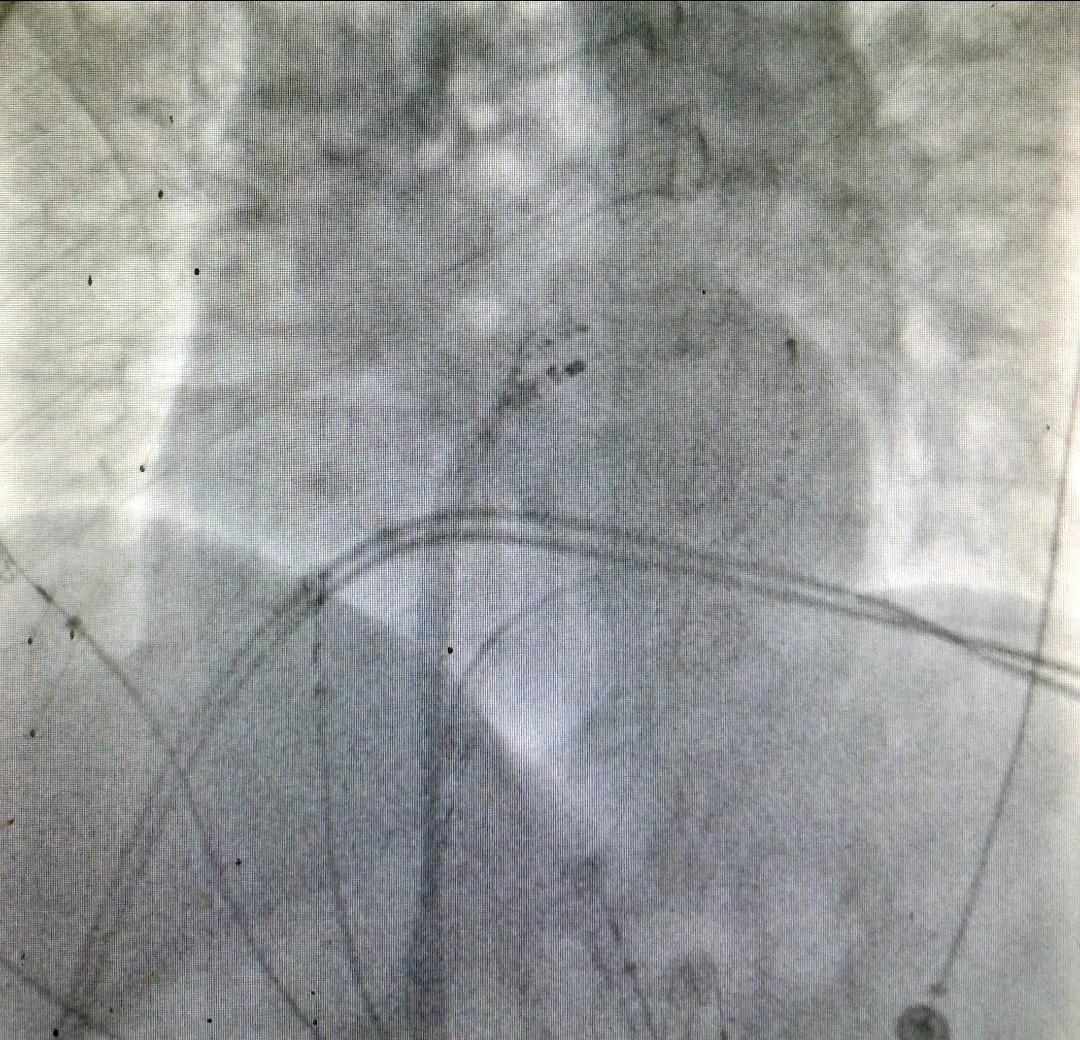

术中X线图

“再换一个体位我看看。”换了两个体位确认穿刺位置后,朱荣清副主任医师轻轻推动穿刺针,然后经针推了一点造影剂,可见造影剂顺着针随着血流消散,清晰显示了左心房,第一针房间隔穿刺成功!轻轻转动穿刺鞘管,换了一个方向,推注造影剂后,右侧肺静脉轮廓清晰地显露出来。同法穿刺房间隔第二针,并完成左侧肺静脉轮廓显影。随后在Ensite三维系统导航下用LASSO环形电极行左房建模、建模、消融,手术一步步进行着。顺着穿刺鞘管,把消融导管顺利送到了左心房,三维模型上一个个红色的消融点紧密排列着,最后围着左、右肺静脉前庭组成了2个圆圈,就像2个防电墙把肺静脉内杂乱无章的电流隔离开了。